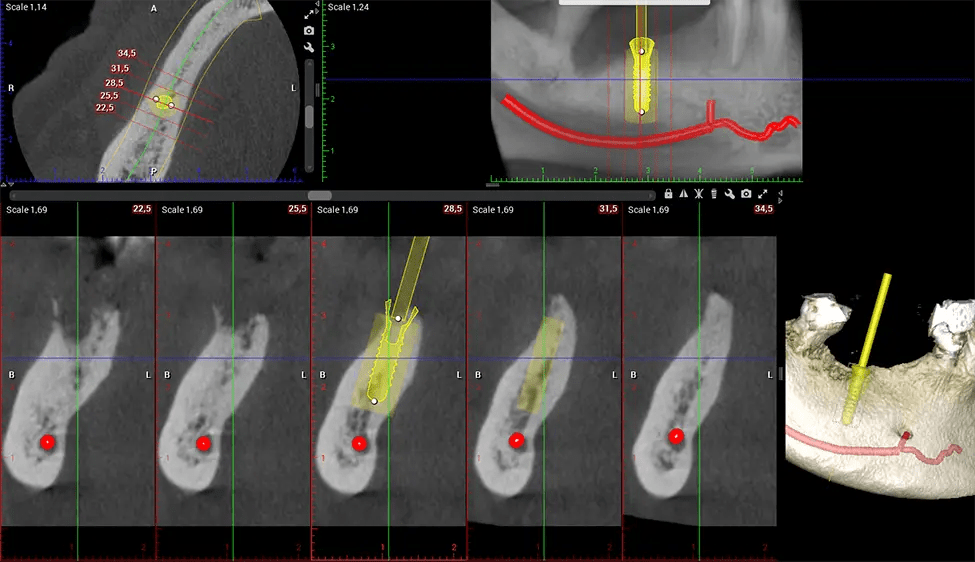

Cone Beam Computed Tomography (CBCT) is an advanced imaging technique used in dentistry and maxillofacial surgery to obtain detailed 3D images of the oral and maxillofacial structures. At Dr G Dental Studio, our CBCT scanners utilize a cone-shaped X-ray beam and a specialized detector to capture images from different angles. A computer then combines these images to create a 3D representation of the patient’s oral anatomy.

There are many benefits to using CBCT technology, especially compared to the traditional 2D X-ray format. One of the most significant advantages of CBCT scans is that they provide much more information than traditional X-rays. A scan lets your dentist see images from all angles of your jaw and mouth, including your sinuses, nasal cavity, cheekbones, and other surrounding areas. This added information helps your dentist craft a comprehensive treatment plan that addresses all aspects of your oral health.

Another significant benefit is that 3D imaging provides more precise images of your bone structure. These images are more detailed, providing you with a more accurate diagnosis. An accurate diagnosis means better treatment for you.

When paired with extractions, dental implant placement, or bone grafting, CBCT technology can provide you with a quicker and much more comfortable experience. This is because the 3D image provides a more detailed picture of your entire oral cavity, allowing your dentist to walk you through each step of the process before it occurs. This often helps patients feel more prepared and comfortable overall, especially if they have had a traumatic experience with past dental treatments.

After the scanning process, the captured X-ray images are processed by the CBCT software, which applies algorithms to reconstruct a detailed 3D image of the scanned area. The software compiles these individual X-ray images and creates a digital 3D representation of the patient’s anatomy. The reconstructed 3D CBCT image can be viewed and analyzed by the dentist or radiologist. This image can be manipulated, rotated, and zoomed in or out to examine specific structures and evaluate the patient’s condition.

Planmeca Viso G7 CBCT ( Cone Beam CT Scan ) is designed to surpass the demands of industry leaders, specialists, and large institutions. It’s has a large ø25×30 cm sensor with four built-in cameras. It can capture unlimited volume sizes from a ø3×3 cm to a ø30x30cm volume capturing the skullcap through C7 on the cervical spine. The Planmeca Viso G7 offers the industry’s largest single volume scan of ø30×19 cm. It’s poised to handle advanced imaging modalities such as Planmeca ProFace® and Planmeca 4D™ Jaw Motion technology. The occipital head support allows an unimpeded view of facial tissue.

Our patented SCARA technology enables doctors to capture True Extraoral Bitewings that are as accurate at detecting caries as a 2D bitewing series, but with half the radiation dose. With our bitewings, doctors can view the apices of teeth on both jaws providing a more comprehensive view of the patients’ anatomy.